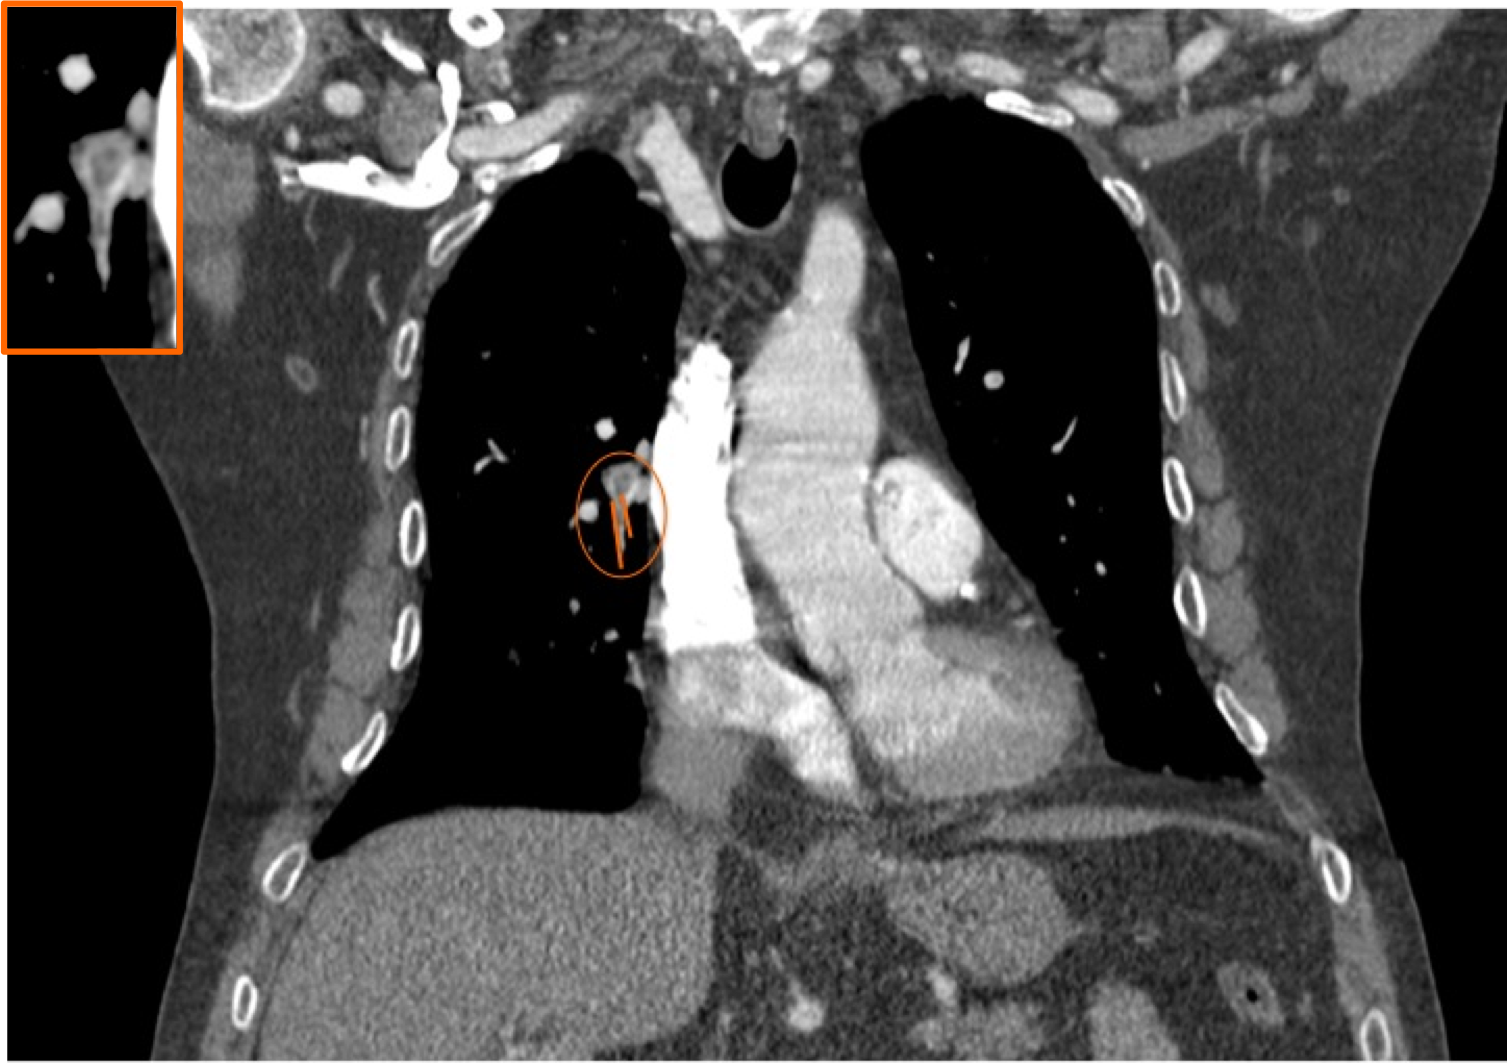

Obstrucción por trombo de la arteria pulmonar principal derecha.

Signo del Cono o Cucurucho en un corte perpendicular del vaso, sugestivo de TEP agudo.

Signo de Rail de tren en un corte perpendicular a la arteria segmentaria del LM, sugestivo de TEP agudo.